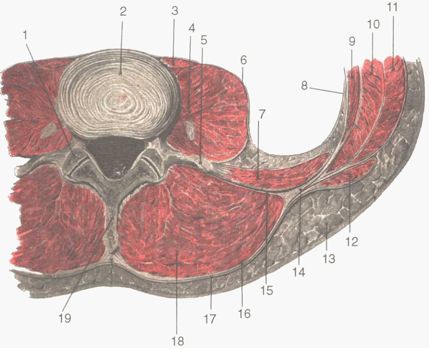

Собственная фасция называется пояснично-грудной (fascia thoracolumbalis). Она состоит из двух листков: поверхностного (lamina superficialis fascia thoracolumbalis), начинающегося от остистых отростков поясничных позвонков, и глубокого (lamina profunda fascia thoracolumbalis), идущего от поперечных отростков поясничных позвонков. Оба листка охватывают мышцу, выпрямляющую позвоночник (m. erector spinae), и по её наружному краю соединяются. Глубокий листок пояснично-грудной фасции в верхних отделах уплотняется и образует пояснично-реберную связку (lig. lumbocostale, s. lig. costotransversarium), натянутую между XII (иногда XI) ребром и поперечным отростком первого поясничного позвонка. Связка ограничивает доступ к почке и в ряде случаев ее приходится рассекать. За глубоким листком собственной фасции спины лежат две мышцы: большая поясничная (m. psoas major) и латеральнее от нее квадратная мышца поясницы (m. quadratus lumborum) (рис.2.1). Первая начинается от боковой поверхности тел XII грудного и I-IV поясничных позвонков, а также от поперечных отростков поясничных позвонков. Опускаясь книзу, большая поясничная мышца соединяется с подвздошной (m. iliacus) и в виде подвздошно-поясничной мышцы (m. iliopsoas) проходит через мышечную лакуну (lacuna musculorum) и прикрепляется к малому вертелу бедра. Вторая мышца берет начало гребня подвздошной кости и прикрепляется к XII ребру, а также к поперечным отросткам нижних поясничных позвонков.

| Рис. 2.1. Мышцы поясницы: 1 – cavum articulare; 2 – fibrocartilago intervertebral is vertebrae lumbalis III et IV; 3 – m. psoas minor; 4 – m. psoas major; 5 – processus transversus vertebrae lumbalis IV; 6 – fascia psoatica; 7 – m. quadratus lumborum; 8 – fascia transversalis; 9 – m. transversus abdominis; 10 – m. obliquus internus abdominis; 11 – m. obliquus externus abdominis; 12 – m. latissimus dorsi; 13 – tela subcutanea; 14 – место отхождения m. transversus abdominis; 15 – глубокий листок fascia thoracolumbalis; 16 – поверхностный листок fascia thoracolumbalis; 17 – fascia superficialis; 18 – m. erector spinae; 19 – processus spinosus vertebrae lumbalis IV. |